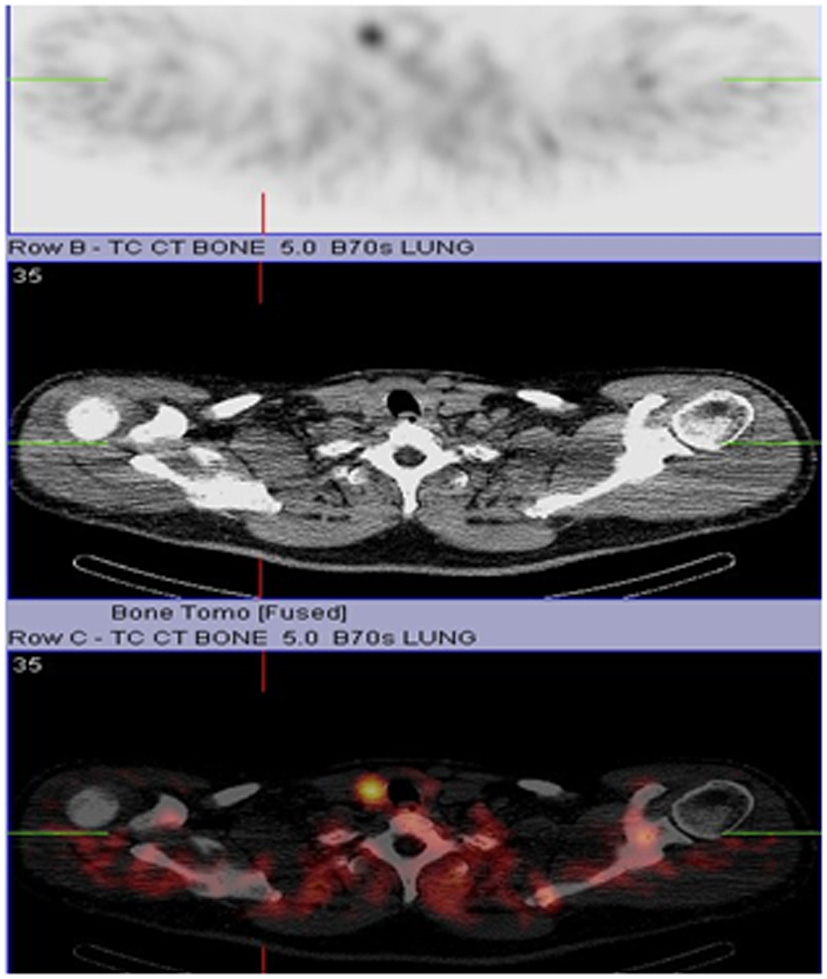

Our patient is a 55-year-old male with history of chronic kidney disease stage III (due to tubulo-interstitial disease, baseline creatinine 1.3 - 1.5), hypothyroidism and hyperlipidemia with diagnosis of primary hyperparathyroidism due to slightly elevated iPTH (53 - 67 pg/ml), persistent asymptomatic mild hypercalcemia (10.4 mg/dl), hypercalciuria (379.5 - 484.1 mg/24 hr), hypophosphatemia (2.7 mg/dl), and low 25-OHD (24.6 ng/ml) who was referred to us for parathyroidectomy. There was no personal history of nephrolithiasis, psychiatric complaints or recurrent fractures. Physical exam of the neck was unremarkable by palpation and inspection. Parathyroid imaging scan showed focal uptake in the inferior pole of the right thyroid lobe. DEXA scan was normal and no stones were found on renal ultrasound. Surgical indication was hypercalciuria per NIH criteria [11]. During surgery, the right thyroid lobe was found to have small multiple nodules at the inferior pole corresponding to the area previously localized by preoperative sestimibi with no obvious parathyroid gland. Four gland exploration was performed and three normal appearing parathyroid glands at the usual locations were found except at the right inferior pole. Bilateral neck exploration to include upper mediastinum, the trachea-esophageal groove, the retro-esophageal, and the carotid sheaths was negative. A small area of paratracheal tissue was removed from the right inferior pole and was reported to be a lymph node. Unable to identify a single parathyroid adenoma on full neck exploration, the neck was therefore closed for further localization studies and potential future re-exploration based on results. Preoperative iPTH, postoperative iPTH and serum calcium were 70.12 pg/ml, 71 pg/ml and 10.5 mg/dl respectively. iPTH and serum calcium remained high postoperatively with peak values of 76 pg/ml and 10.7 mg/dl respectively. Repeat parathyroid scan together with single photon emission computed tomography (SPECT) and non-enhanced computer tomography of the upper chest showed increased activity in the mid to inferior portion of the right thyroid lobe at both phases (Fig. 1 and Fig. 2 respectively). Additionally, the SPECT demonstrated increased activity corresponding to a poorly defined hypodensity in the right lobe of the thyroid now suggesting an intrathyroidal parathyroid gland. Thyroid ultrasound showed two hypoechoic nodules or one bi-lobed nodule measuring 1.3 x 1.3 x 1.2 cm (anterior) and 1.1 x 1.2 x 1.2 cm (posterior) which were very close to each other at the inferior right thyroid pole (Fig. 3). Fine needle aspiration with iPTH washings of the anterior thyroid nodule showed iPTH of 236,432 pg/ml (normal non-parathyroid tissue < 30) but cytology was not possible due to insufficient cellularity. Patient was immediately started on cinacalcet 30 mg/day after the above results and the diagnosis was now confirmed as an intrathyroidal parathyroid tumor. He was taken back to the operation room electively and now underwent an uncomplicated right thyroid lobectomy with isthmusectomy. Preoperative and immediate postoperative PTH were 49.19 and 12 pg/ml respectively. Patient had transient decrease in PTH post-operatively and was discharged home with calcium supplement while awaiting PTH to normalize. Patient was seen in clinic postoperative day 13 without complaint, where PTH was 13 pg/ml and serum calcium 9.2 mg/dl. At 3-months follow up, serum was 8.8 mg/dl and doing well. The final pathology specimen revealed intrathyroidal parathyroid carcinoma, with negative margins, and the resection of right paratracheal lymph node at the original operation was negative for any regional nodal metastasis.

![]() Click for large image | Figure 2. CT/SPECT |